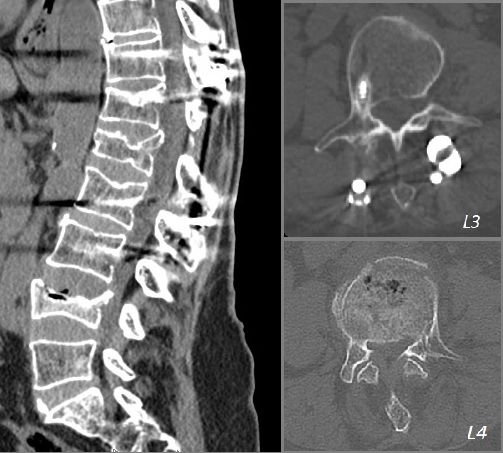

L4 vertebroplasti sonrası direkt grafiler.